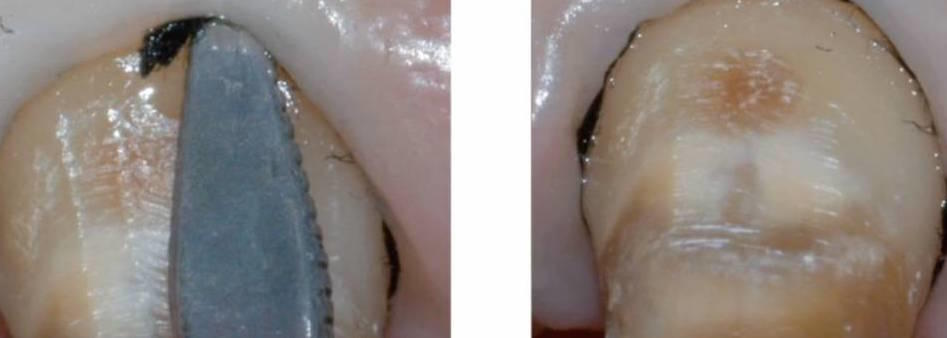

• La preparazione a finire

• La ricostruzione periferica dei monconi su denti naturali

• Controllo e miglioramento della precisione delle corone metalliche